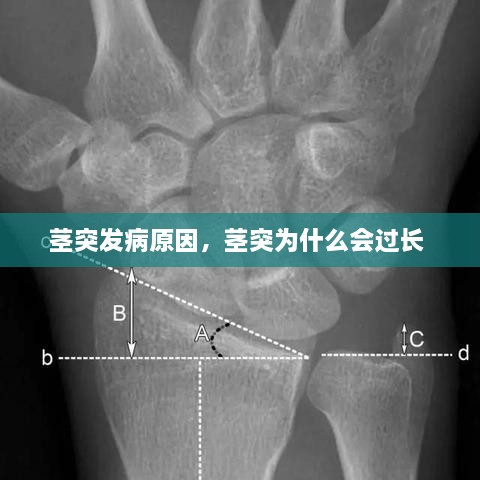

莖突過長是莖突癥最常見的原因之一。當(dāng)莖突的長度超過正常范圍時,可能會對周圍的神經(jīng)、血管或肌肉造成壓迫,引發(fā)癥狀。這種異??赡苁怯捎谶z傳因素、胚胎發(fā)育異?;蚝筇焐L異常導(dǎo)致的。